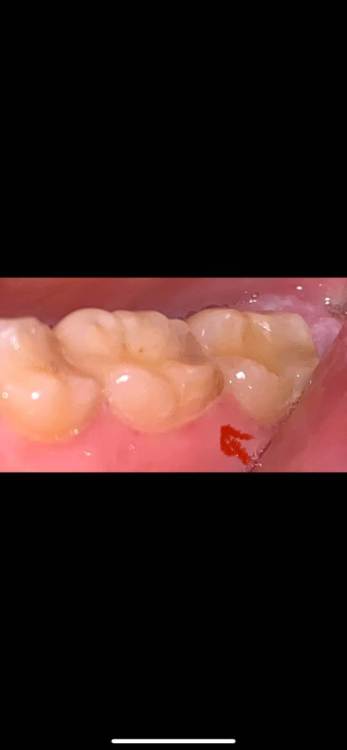

vanessa120 Опубликовано 18 марта, 2023 Поделиться Опубликовано 18 марта, 2023 Недавно появилось легкое пульсирующее ощущение в боковой части лица, иногда я чувствую боль (я думаю) в зубе, но она приходит и уходит, просто чувствует себя немного странно? Не болит при надавливании или что-то в этом роде. Это просто воспаленная десна или что-то более серьезное? Это похоже на карьес, но я не могу позволить себе ходить к стоматологу в данный момент. Очень туго с деньгами. У меня клиническая депрессия, поэтому мое здоровье полости рта не очень хорошее. Какие-нибудь домашние средства, которые могли бы сработать? Я прикрепил фотографии. я не пью и не курю Ссылка на комментарий

shishok Опубликовано 19 марта, 2023 Поделиться Опубликовано 19 марта, 2023 Похоже на вторичный кариес под пломбой. Хорошо бы снимок посмотреть. Кариес лучше полечить побыстрее (может заболеть в любой момент). Ссылка на комментарий